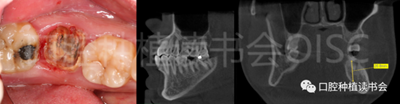

患者為70歲女性,右下后牙樁核冠因遠(yuǎn)中牙根縱裂脫落,全身健康狀況良好,輕度骨質(zhì)疏松??趦?nèi)檢查:47殘根,遠(yuǎn)中根縱裂,部分根面已腐至齦下2mm,叩(++),松(-);48近中傾斜阻生,咬合關(guān)系、修復(fù)間隙及牙周情況正常(圖12)。

圖12 遠(yuǎn)中根縱裂及根面齲導(dǎo)致47殘根無法保留。

術(shù)前CBCT(美亞光電)檢查:47根分叉下方骨高度及骨寬度滿足即刻種植要求(圖13)。

圖13 47根分叉區(qū)骨寬度及骨高度(與下頜神經(jīng)管之間的距離)滿足即刻種植要求。